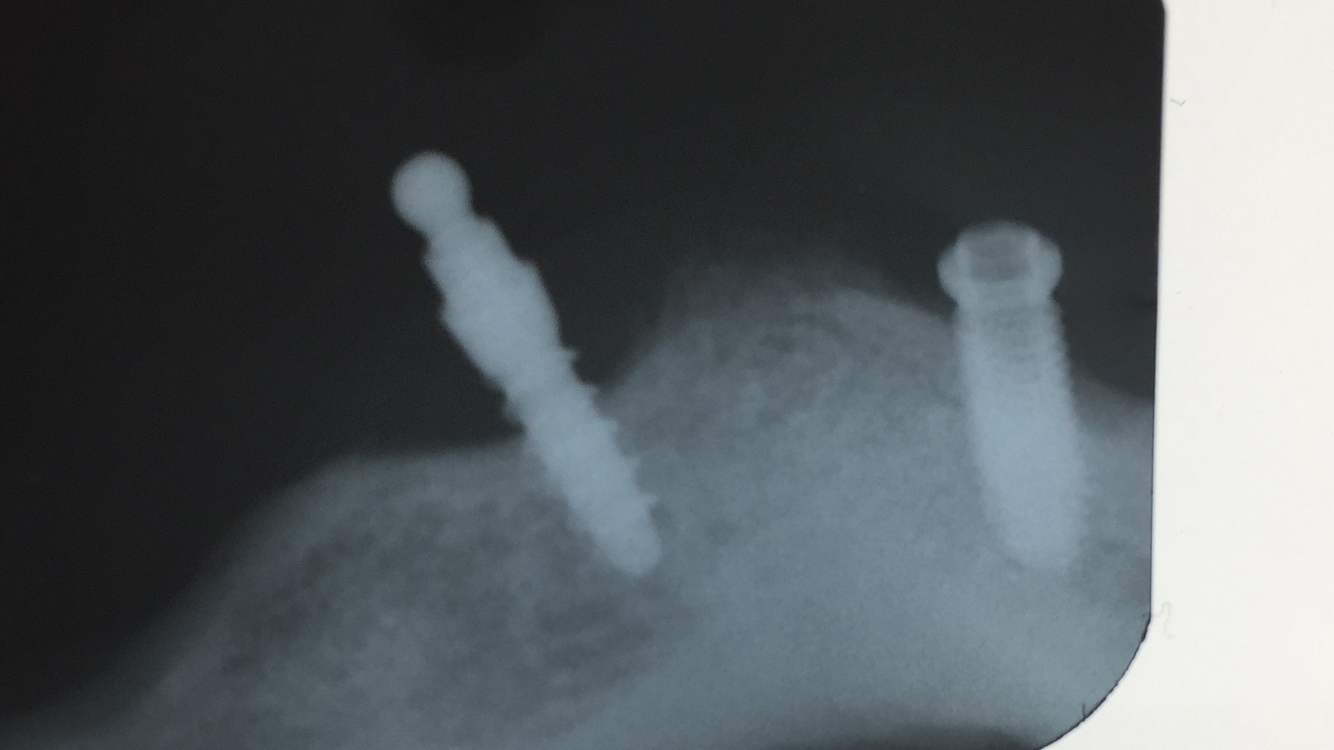

Implantes 47 y 35

No se que implantes son ‘. Los pusieron en i Dental De Alicante . Gracias